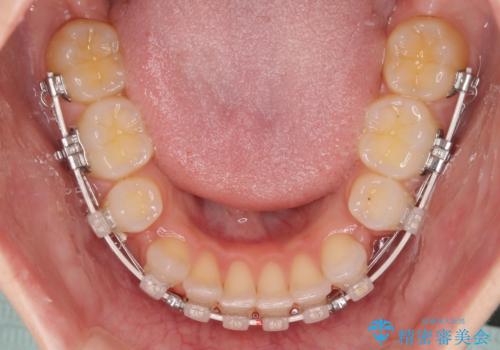

- 矯正装置

- 審美装置

- 前歯のデコボコとクロスバイトを気にして来院された患者様です。

上下ともにデコボコはそれほど強くありませんでしたが、非抜歯では口元が突出した仕上がりとなる可能性があるため、上下左右の第一小臼歯4本を抜歯し、ワイヤー装置での抜歯矯正を行うこととしました